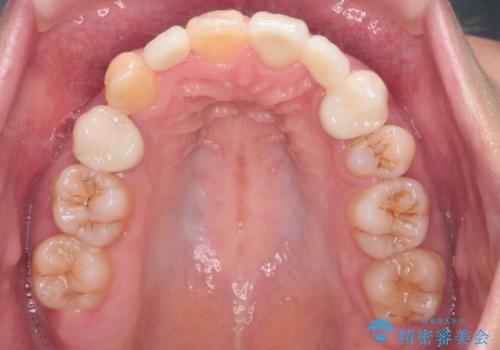

矯正治療で歯並びを治した後、乳歯を抜いたところにブリッジを入れています。

左上の奥歯はすれ違っていたためそのかみ合わせも整えています。

歯を抜いて治療を行ったため、Eラインが整った形で治療ができました。口が断然閉じやすくなっています。